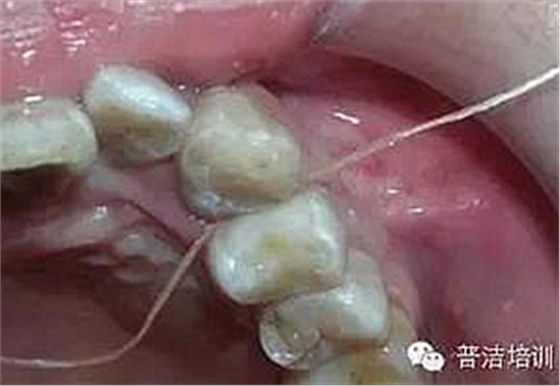

牙線去除鄰面樹脂粘結(jié)劑

鄰面拋光